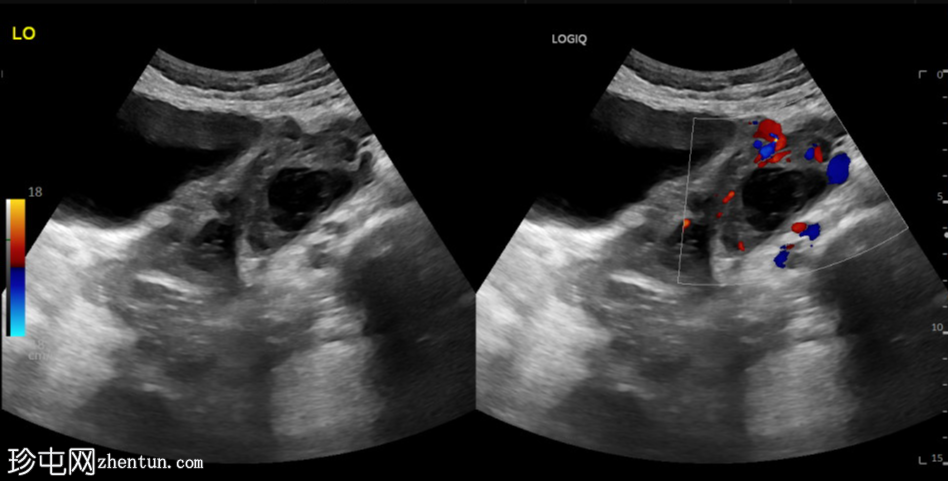

超声检查

斜切面

左侧卵巢明显增大,可见一囊肿,大小约3.2 x 2.3 cm,呈火环征,可能为黄体囊肿。左侧卵巢与子宫之间可见一管状结构,直径约1.3 cm,内含浑浊液体,未见血管,最可能为输卵管积血。以上特征提示可能为左侧异位妊娠。

未见宫内妊娠囊。